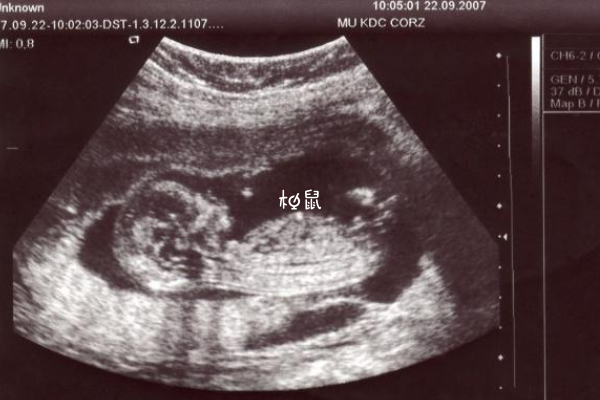

B超有两点基本是男孩说的是B超图像上,胎儿双腿之间的区域,也就是胎儿性别特征的地方,如果能观察到有明显的两个白点的话,说明准妈妈怀的可能是男孩,如果是三条白线的话,说明准妈妈怀的是女孩。两点对应的是男孩的生殖特征点,说明怀男孩可能性大。

两点对应的是男孩的生殖特征点,说明怀男孩可能性大,在民间还有三条线的说法,如果看到图像上双腿间有黑线、黑杠或者是明显的白线的话,那是女宝宝的生殖特征点,不过医生在检查的时候,会避开宝宝的生殖器,正常情况下准妈妈是看不到这样明确的男女标志,所以不能通过这个方法分辨男女。

在孕早期或者孕12周左右做B超、彩超检查,看到宝宝双腿间有两个圆球状的东西或者是一个小肠状的东西,说明可能是一个男孩,如果准妈妈看到宝宝双腿之间是三根横线或者是一个小凹槽,说明准妈妈可能怀女孩。